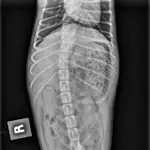

Prompted by history and examination, abdominal radiography was performed. Radiographs showed moderate distention of the stomach with a coarse, uniformly mottled opacity with well-defined margins. There were no small intestinal abnormalities. A small mineral opaque foreign body was present in the colon.